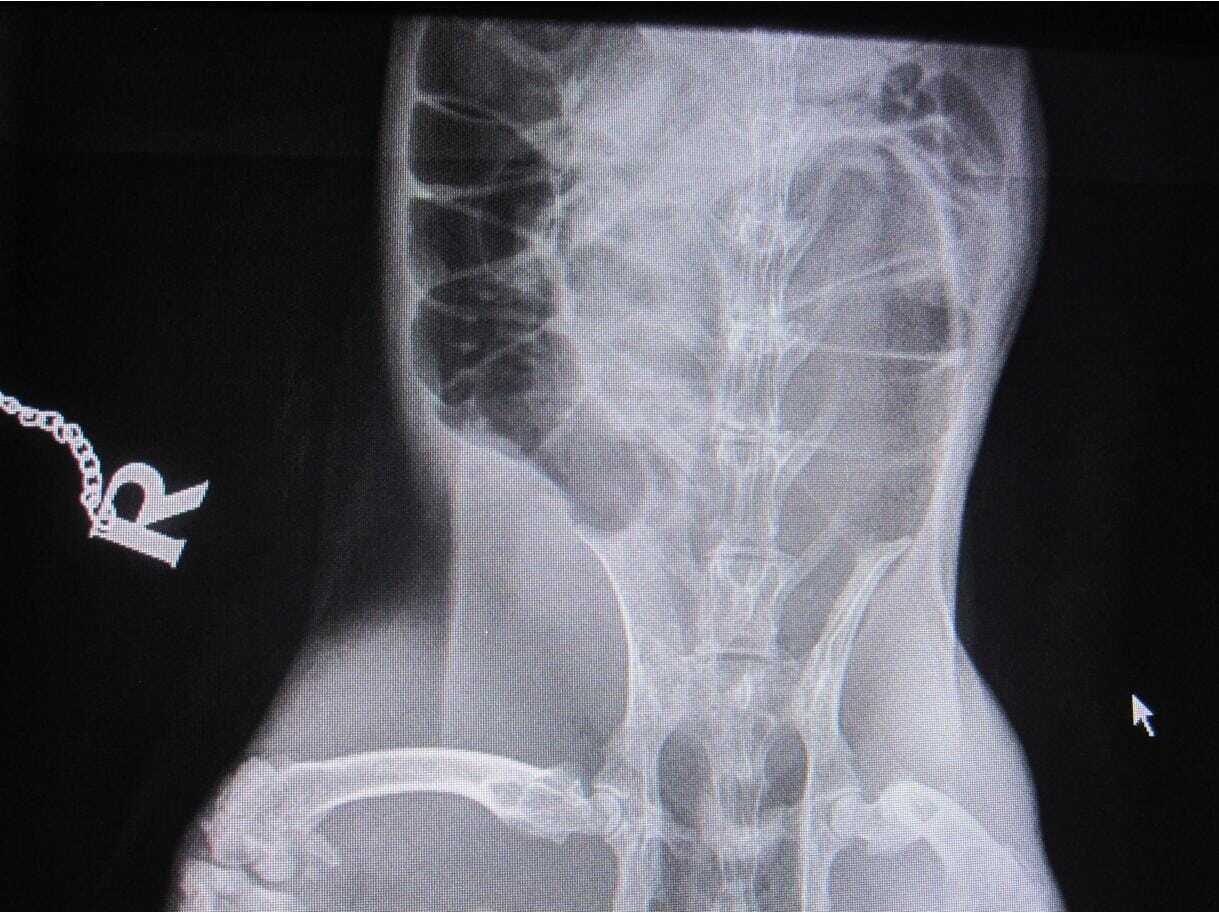

Where an obstruction is suspected, it is useful to check a blood glucose level. Rabbits that have very high blood glucose when in gut stasis are more likely to have a gut obstruction, although this is not diagnostic. If the blood glucose is high, then X-rays (Figures 1 to 3) or ultrasound should be used to further rule in or out an obstruction.